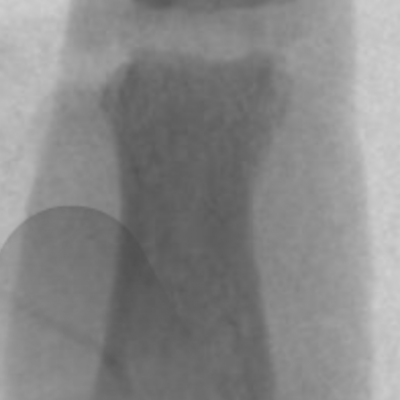

Joint replacement

Joint replacements can use many types of materials including silicone, metal and plastic and pyrocarbon. Silicone joint replacements have been used in the small joints of the hand since the early 1960’s. They have a long track record and have a predictable outcome and ability to exchange implants if they fail. Modern day Metal on plastic implants have evolved since 1979 and now resemble modern day “mini knee replacements”. Pyrocarbon is a newer material and has been used since 2000. It can be implanted as a total joint replacement or hemiarthroplasty (replacing only one damaged side of the joint). Most joint replacement surgeries provide good relief of pain whilst maintaining motion however it is difficult to reliably improve range of motion in very stiff fingers.